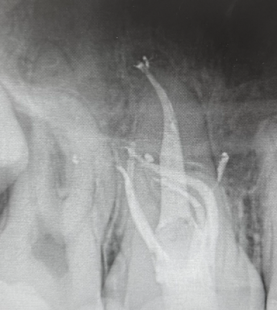

- Rationale for dental implants

- Surgical and Prosthetic implantology

- Immediate implants (when and why)

- Understand the Fundamentals of Implant Dentistry:Gain a comprehensive understanding of the key concepts of implant dentistry, including patient selection, surgical anatomy, and tissue handling, essential for safe and predictable implant placement.

- Master Implant Surgery Protocols:Learn the step-by-step procedures for proper drilling protocols and implant placement, emphasizing the importance of precision and technique in achieving optimal results.